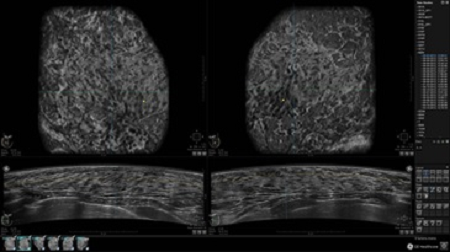

• Многооконный просмотр: 4 - 12 изображений

• Оптимизированные протоколы обзора для большого потока пациентов

• Стандартизованная ориентация изображения: «толстый срез» в коронарной плоскости; поперечная; сагиттальная плоскость; радиальный и антирадиальный поворот изображения; просмотр исключительно области интереса

• Одновременный просмотр двух изображений для сопоставления в коронарной плоскости